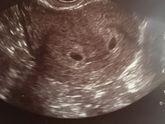

Приехала я значит на море, первые два дня все замечательно. А сегодня с раннего утра тошнит пипец как! Уже 4 раза стошнило ?(простите за подробности), есть вообще ничего не могу, только воду пью! Отравления быть не может точно, ничего нового не ела…Как … Читать далее